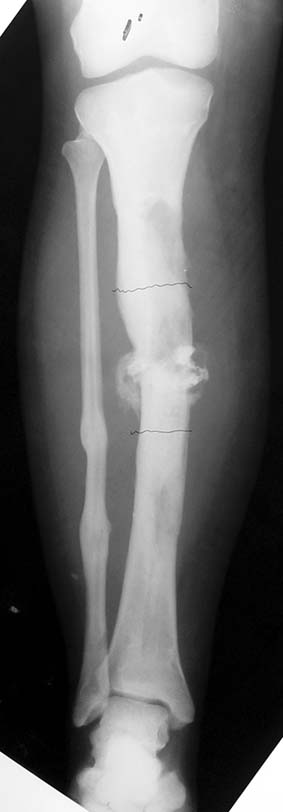

Appropriate radical debridement necessitates excision of all necrotic bone and soft tissues, and frequently causes instability at the involved extremity. The remaining bone and soft tissue defect has to be fixed and reconstructed. The distraction osteogenesis method of Ilizarov is used successfully for achievement of union, correction of the deformity, elimination of limb length inequality and reconstruction of segmental bone defects.

The duration of external fixation (external fixation index) depends on the amount of distraction required, and the extremity is prone to complications during this period. After the distraction phase is completed, the external fixator remains in place during the consolidation phase, which lasts twice as long as the distraction phase; but this period is hardly tolerated. If the external fixator is removed before sufficient consolidation is achieved, fractures, deformity and shortness will be the result. In our department, ‘lenghthening over nail’ method is used in order to decrease the external fixation index and increase patient comfort and activity level. In this method, the intramedullary nail is statically locked after the completion of the distraction phase, and external fixator is removed. The extremity is stabilized by the intramedullary nail during consolidation phase. In this way, complications due to long external fixation index or early removal of the external fixator are avoided.